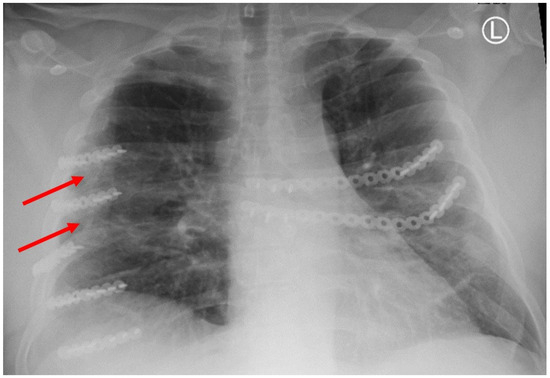

Figure 1. Chest X-ray showing HO at the tips of the red arrows.

HO was noted in nine patients (43%) and seen as early as 8 months post-operatively. Overall, 15% (32/208) of rib fractures showed evidence of HO at follow-up. In patients that developed HO, 36% (32/88) of rib fractures had evidence of HO formation. The HO was evident on posterior–anterior chest X-ray in 25% (2/8) of patients. No significant difference was noted in patients with HO when accounting for gender (43.8% vs. 56.3%, p = 0.647), ISS (24 ± 12 vs. 18 ± 9, p = 0.265), flail chest injury (36.4% vs. 63.6%, p = 0.425), number of fractures (8 (4–16) vs. 9 (3–21) p = 0.917), polytrauma (44% vs. 50%, p = 0.801),time to follow-up CT scan (18.0 (7.7–88.5) vs. 14.2 (7.1–56.7) p = 0.247), or number of SSRF plates (4 (3–11) vs. 5 (3–11) p = 0.862). The number of patients with traumatic brain injury was similar, with three patients in both groups. A significant difference in these patients was identified when comparing approach to screw fixation pre-drilling with self-tapping (ST) screws versus self-drilling (SD) screws (89% vs. 11%, p = 0.024), year of operation (2107 ± 1.9 vs. 2020 ± 1.7, p = 0.004), and operative day (6 (0–9) vs. 2 (2–5), p = 0.023). All patients were treated with non-steroidal anti-inflammatory medications after injury (ibuprofen). The difference in patients with HO and the difference in types of screws used are illustrated in Figure 3.